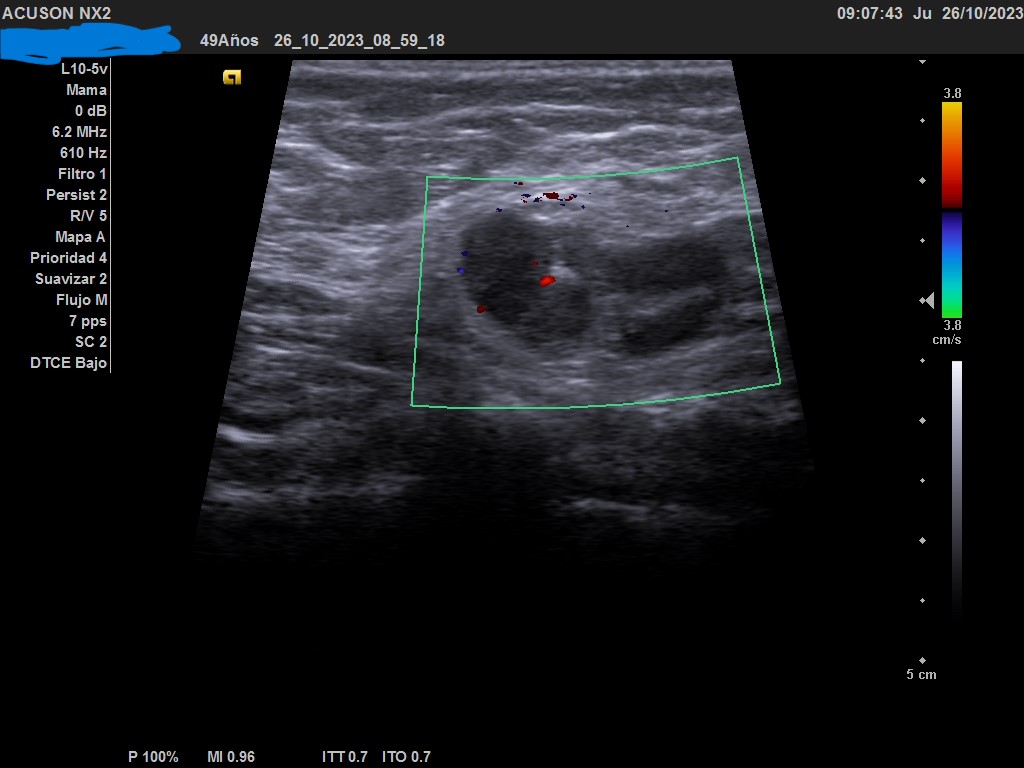

Ecografía: mama izquierda se observa tumoración hipoecogénica lobulada en cuadrante superior externo de aproximadamente 4 cm, heterogénea, que capta al Doppler color y dos adenopatías de aspecto reactivo en axila homolateral. Imagen sospechosa de malignidad.

Ecografía de mama hospitalaria: Se confirma en mama izquierda masa sólida palpable de al menos 56 mm, de contorno mal definido, sospechosa de malignidad. Se realizará BAG ecoguíada, y adenopatías axilares izquierda de aspectos patológico. PAAF de ganglio izquierdo dirigida por ecografía: Citología positiva para malignidad. Compatible con metástasis de carcinoma. Biopsia BA Tipo histológico: Carcinoma infiltrante. Grado histológico: Grado III, pobremente diferenciado.